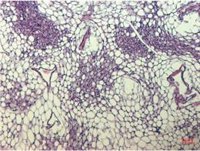

En concreto, los grupos de investigación DIAMET e IBODI del IISPV, responsables de liderar este estudio, han encontrado que, en estos pacientes, el tejido adiposo de la mucosa intestinal (la parte que tienen más dañada) experimenta un proceso de conversión (browing) en su color, pasando de ser blanco a ser beige.

Este tipo de tejido adiposo beige es común en los bebés, pero se va perdiendo a medida que crecemos. Además, en varios modelos animales se ha constatado que tenerlo aumentado protege al organismo ante la obesidad, la diabetes o enfermedades inflamatorias, y, por tanto, es beneficioso para la salud.